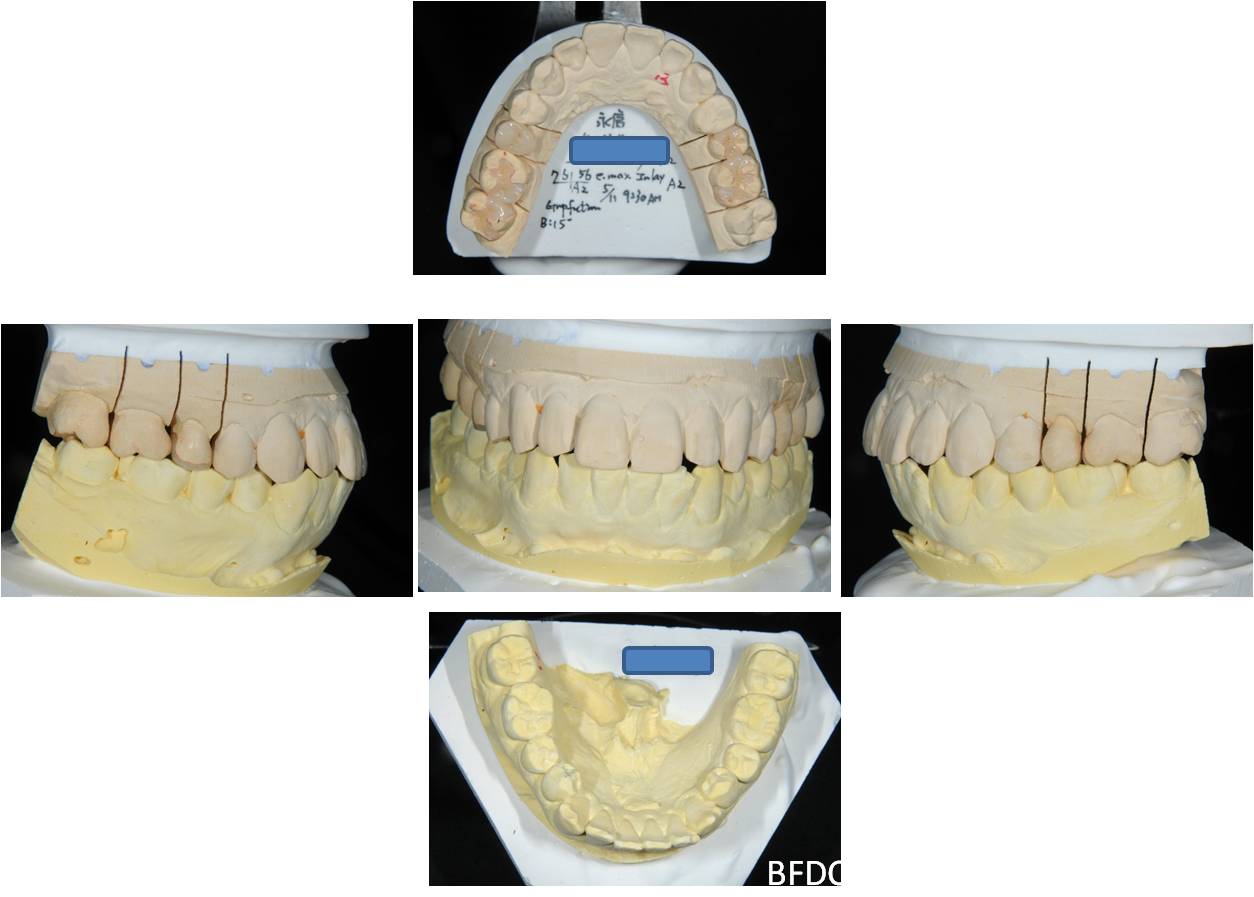

陶瓷崁體及冠蓋體-蛀牙-#1516172526 大範圍的補皮,該如何選擇,嵌體的方式就適用於大範圍的填補,因為它是一體成形, 嵌體材質多種,以往才會使用黃金合金,但因價格昂貴且顏色太過突出,因此現在多使用玻璃陶瓷二氧化鋯等材質的全瓷冠。嵌體有其優勢,因一體成形的材料,硬度和穩定性都較高,不用一點一點填補,減少下方凹陷重複蛀牙的危機,也不會變形或染色,美觀度高很多。 #1516172526蛀牙 #1516172526蛀牙 崁體及冠蓋體修形 安裝模型至咬合器 嵌體及冠塊體製作 陶瓷崁體及冠蓋體 黏著後 黏著後X光 術前、術後比較 嵌體有其優勢,因一體成形的材料,硬度和穩定性都較高,不用一點一點填補,減少下方凹陷重複蛀牙的危機,也不會變形或染色,美觀度高很多。

能避免片狀樹脂造成的,下方重複蛀牙,或彈性大造成咬合不舒服的問題,若有多顆牙齒填補,或坑陷較大者,如牙齒已蛀超過1/2或2/3者,才建議使用此種方式。